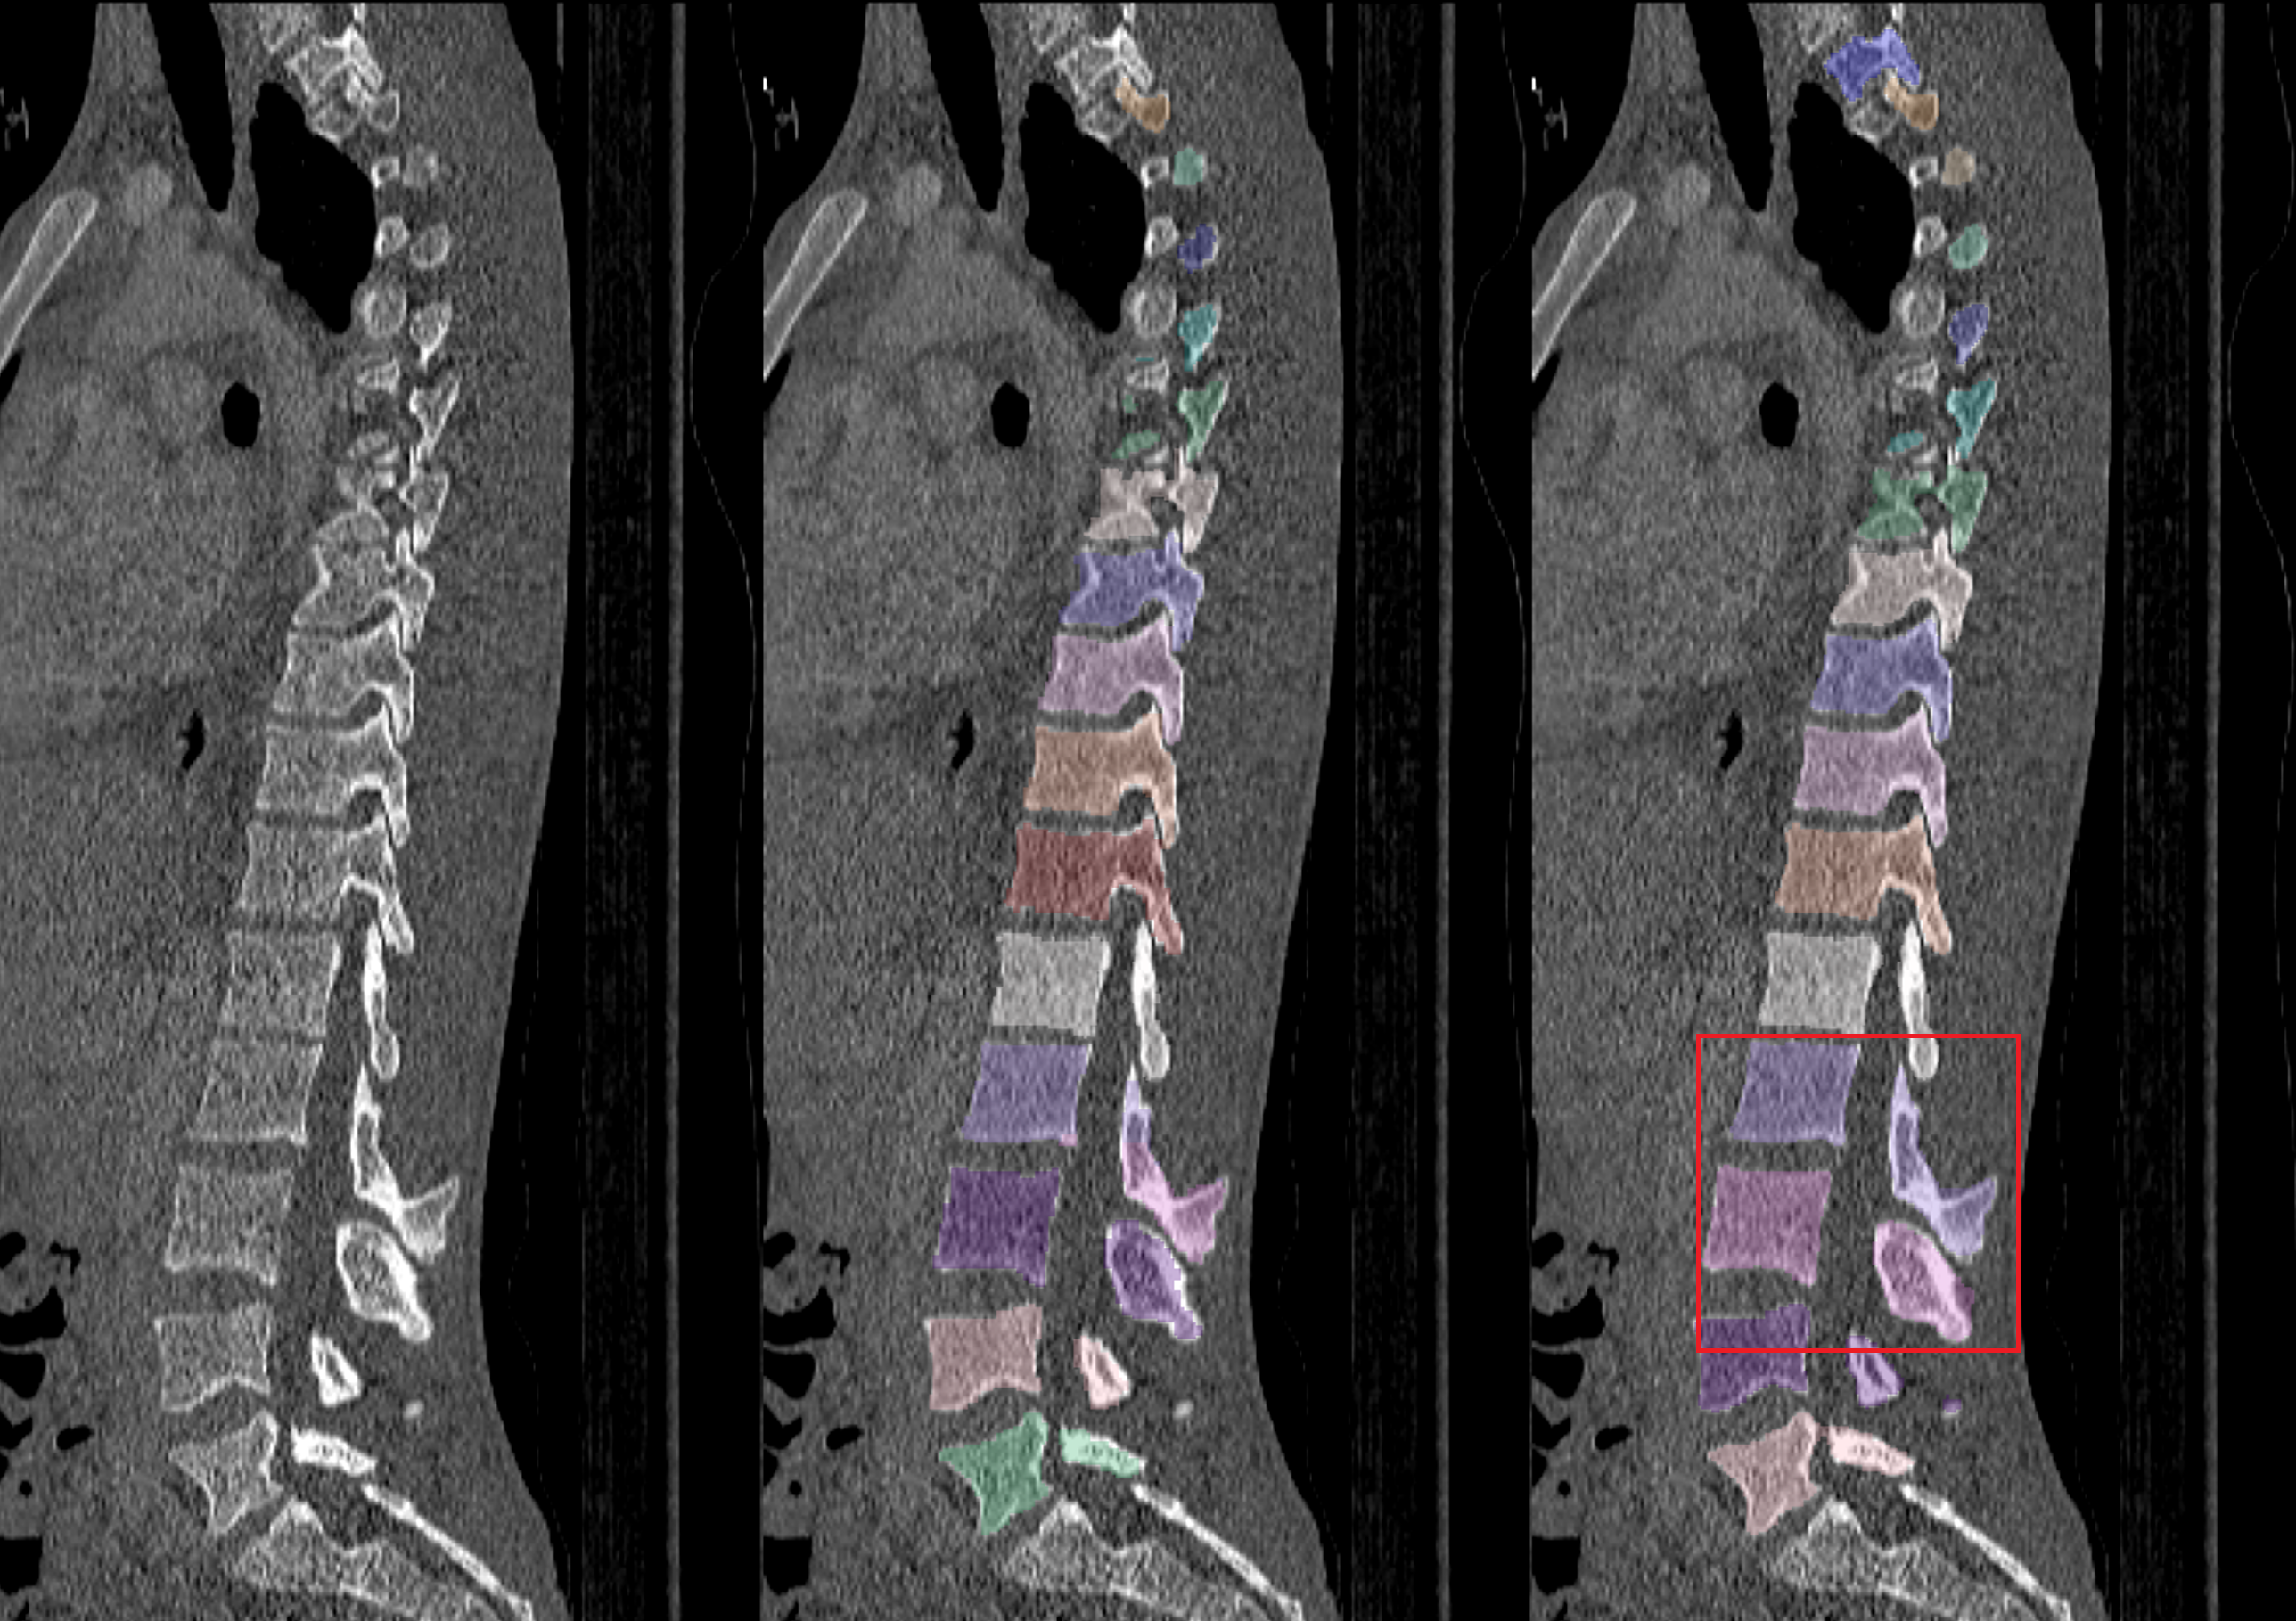

4.2 Vertebral Localization and Segmentation

We evaluated the model on the test sets from the VerSe2019 and VerSe2020 datasets. These test sets contain 113 subjects in total. Each CT volume was pre-processed by smoothing with a Gaussian kernel with σ\sigma = 0.75 mm to reduce noise.

The models have 22.91 million parameters for spine localization, 21.13 million parameters for vertebrae localization, and 17.19 million parameters for vertebrae segmentation. The inference time varies with the field-of-view and the number of visible vertebrae in the CT volume. All experiments were conducted on a dual-socket Intel® Xeon® Platinum 8462Y+ system (64 physical cores, 2.80 GHz, 120 MiB L3 cache) running Linux. On the combined test set of 113 subjects, the average inference time per volume was about 1 min 40 s. Specifically, the process took about 3 s for spine localization, 19 s for vertebrae localization, and 1 min 17 s for vertebrae segmentation. The visualization of vertebral localization and segmentation is shown in Figure 3.

(a) Original CT Image

(b) Segmentation Result

(c) 3D Mesh

Figure 3: Visualization of vertebral localization and segmentation results.

Although the model demonstrated high performance overall, we observed several failure cases. In some cases like Figure 4a, vertebrae were missed completely. This is because vertebral centroids that are too close in z axis may cause blurred boundaries in segmentation, so these vertebrae centroids are deleted in the post-processing. In some cases like Figure 4b, vertebrae were mismatched to incorrect labels due to rare vertebral mutation, or like in Figure 4c, due to artifact of metal implants. These issues highlight the challenges of accurate vertebra detection and segmentation in complex clinical scenarios.